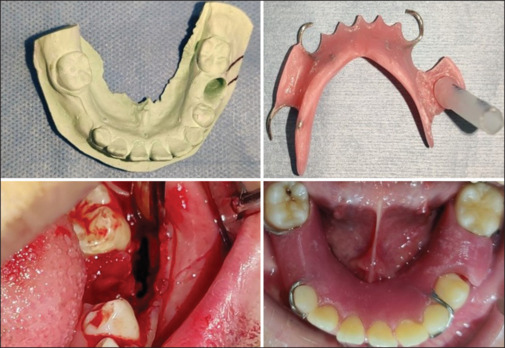

根性囊肿是颌面部最常见的炎性囊肿之一,起源于赫氏上皮根鞘的残余。这些通常被诊断为x线片上的偶然发现,很少有症状并且进展缓慢。减压可以作为一种保守治疗方法用于治疗儿童大根性囊肿,以获得满意的愈合和对邻近重要结构的最小损害,同时允许继发牙齿的爆发。本文讨论了一名12岁儿童的大根状囊肿的治疗方法,该囊肿引起下颌管移位和牙胚发育,通过减压导致骨愈合和移位的连续前磨牙自发爆发,并定期随访40个月。虽然减压是一种众所周知的方法,但本病例的长期随访强调了小儿神经根囊肿病例自然愈合的潜力,使解剖恢复正常,没有任何功能损害。本文还强调了定期临床和影像学随访对牙髓治疗的非生命乳牙的重要性。

Radicular cysts are one of the most common cysts of inflammatory origin involving the maxillofacial region that arise from the remnants of Herwig's epithelial root sheath. These are often diagnosed as incidental findings on radiographs, which are seldom symptomatic and are slowly progressive. Decompression could be used as a conservative treatment approach for the management of large radicular cysts in children to have satisfactory healing and minimum damage to adjacent vital structures, simultaneously allowing the eruption of succedaneous tooth. This paper discusses the management of a large radicular cyst in a 12 year old, causing displacement of the mandibular canal and developing tooth germ using decompression that resulted in bony healing and spontaneous eruption of displaced succedaneous premolar, with a periodic follow-up for 40 months. Although decompression is a well-known approach, the present case with long-term follow-up emphasizes the potential of spontaneous healing in pediatric radicular cyst cases restoring the anatomy to normal without any functional impairment. This paper also highlights the importance of periodic clinical and radiographic follow-up in pulpally treated nonvital primary teeth.